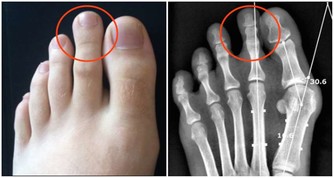

濕氣所引起的疾病大致分為風濕類疾病、皮膚疾病、婦科疾病、胃腸道疾病、心腦血管疾病。會出現關節酸痛、頭暈胸悶、全身乏力、噁心乾嘔的症狀,嚴重的會影響女性的生理健康,引起嚴重的婦科疾病,例如月經不調、白帶異常、下陰瘙癢有異味等等。